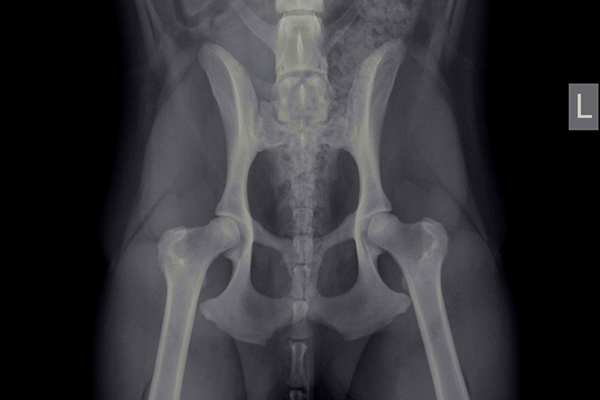

Heupdysplasie (HD)

Onder heupdysplasie wordt het volgende verstaan: een te ondiepe heupkom, waardoor de heupkop te veel ruimte heeft om te bewegen. Er is niet één enkele oorzaak voor te geven; meestal is het een combinatie van snelle groei, inspanning, voeding, leefomstandigheden en erfelijke factoren. Bij erfelijke factoren bestaat een aangeboren dysbalans tussen de spieren van het heupgewricht en de groei van bot, waardoor de heupkop niet goed in de kom wordt getrokken. Wat volgt is een abnormale ontwikkeling van het heupgewricht, wat kan leiden tot instabiliteit en daardoor irritatie van het gewrichtskapsel en het kraakbeen op de heupkop met artrose (=slijtage) als eindresultaat.

Artrose aan de heupen uit zich in het algemeen in bothaakjes aan de heupkop, verbreding van de hals van de heupkop (= de aansluiting van de heupkop met de rest van het dijbeen), onregelmatigheden in het bot van de heupkom en luxatie van de heupkop ten opzichte van de heupkom (heup geheel of gedeeltelijk uit de kom).

Met behulp van röntgenfoto’s kan de diagnose worden gesteld.

HD-foto’s en beoordeling door de Raad van Beheer

Het is mogelijk om rashonden op 12 of 18 maanden leeftijd te laten testen op heupdysplasie door het maken van röntgenfoto’s van de heupen (onder sedatie). Deze foto’s worden dan door de Raad van Beheer beoordeeld. Belangrijk is dat het stamboomnummer van het dier bekend is, evenals het chipnummer en de volledige (stamboom)naam van het dier.

HD-status

HD A (HD -)

Röntgenologisch vrij van heupdysplasie, dit betekent niet dat de hond geen drager kan zijn van de afwijking.

HD B (HD tc)

(Overgangsvorm) zijn geringe veranderingen passend bij heupdysplasie, maar die bij de fokkerij niet van belang te zijn.

HD C (HD ±)

(Licht positief) duidelijke veranderingen, passend bij het ziektebeeld van heupdysplasie.

HD D (HD +)

(Positief) duidelijke veranderingen, passend bij het ziektebeeld van heupdysplasie.

HD E (HD ++)

(Positief in optima forma) ernstige misvormingen van het heupgewricht.

De afwijkingen die op de röntgenfoto’s te zien zijn, komen niet altijd overeen met de last die de hond van deze aandoening heeft. Honden met aanmerkelijke afwijkingen zijn soms klachtenvrij, terwijl andere honden, met flinke pijn- of bewegingsklachten, soms slechts een beperkte afwijking op de röntgenfoto’s laat zien.